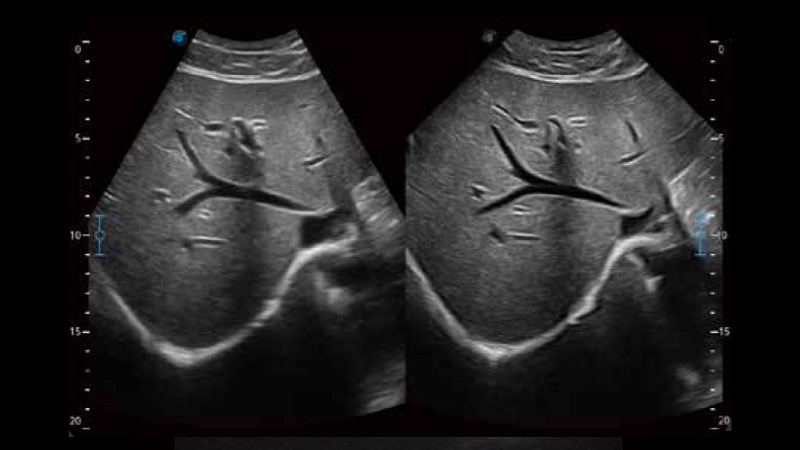

实时宽景成像技术

通过彩色血流和实时宽景相结合,可观察到完整的动静脉血流,方便医生检查。实时扫查过程中,如有任何操作失误也可以很容易地进行回扫擦除,而不会中断扫查。